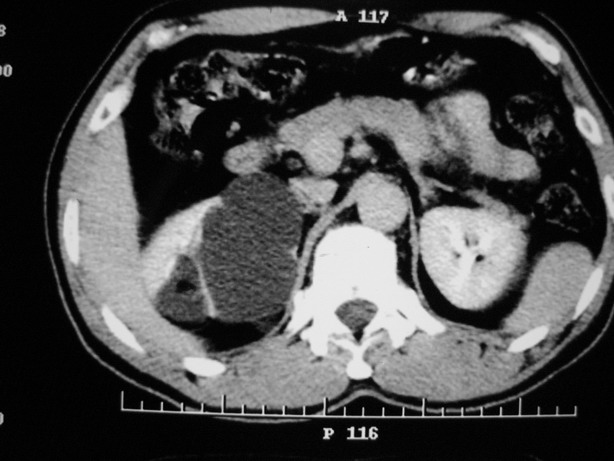

男性,48,体检发现,平时无症状。

平扫:

肾盂旁多囊性占位,有实性成分,增强有轻度强化,收集期病变内无造影剂显影。诊断肾盂旁囊肿,有实性成分无法解释,查书后诊断为:多房性囊性肾瘤!!不知大家同意否?????????对本病知道不多,望大家不吝赐教!!